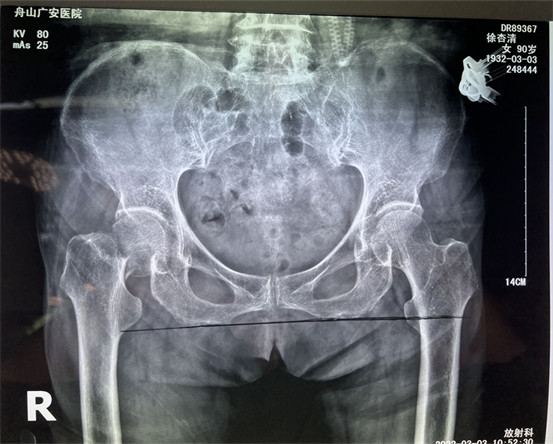

幾周之前,90歲高齡的老太太行走時(shí)不慎摔倒,發(fā)生股骨頸骨折,合并心臟病等多種內(nèi)科疾病。股骨頸骨折的危害極大,常發(fā)生于七十、八十歲嚴(yán)重骨質(zhì)疏松的老年人,如果不能給以合適的手術(shù)治療患者會(huì)喪失行走能力,同時(shí)臥床時(shí)間長會(huì)才出現(xiàn)許多并發(fā)癥,危及生命。

在舟山廣安醫(yī)院辦理住院后,經(jīng)過白黎明副主任和骨科中心羅軍主任的系統(tǒng)檢查和全面評估后,決定為患者做了微創(chuàng)智能DAA人工髖關(guān)節(jié)置換。